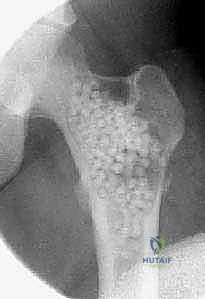

تُظهر هذه الأشعة السينية كيس عظم متمدد (ABC). لاحظ التوسع الكبير في العظم وترقق القشرة العظمية مقارنة بالكيس أحادي الغرفة.

في الـ ABC، تظهر الآفة غير مركزية، متمددة، وتدفع قشرة العظم للخارج لتصبح رقيقة جداً مثل "قشرة البيضة".